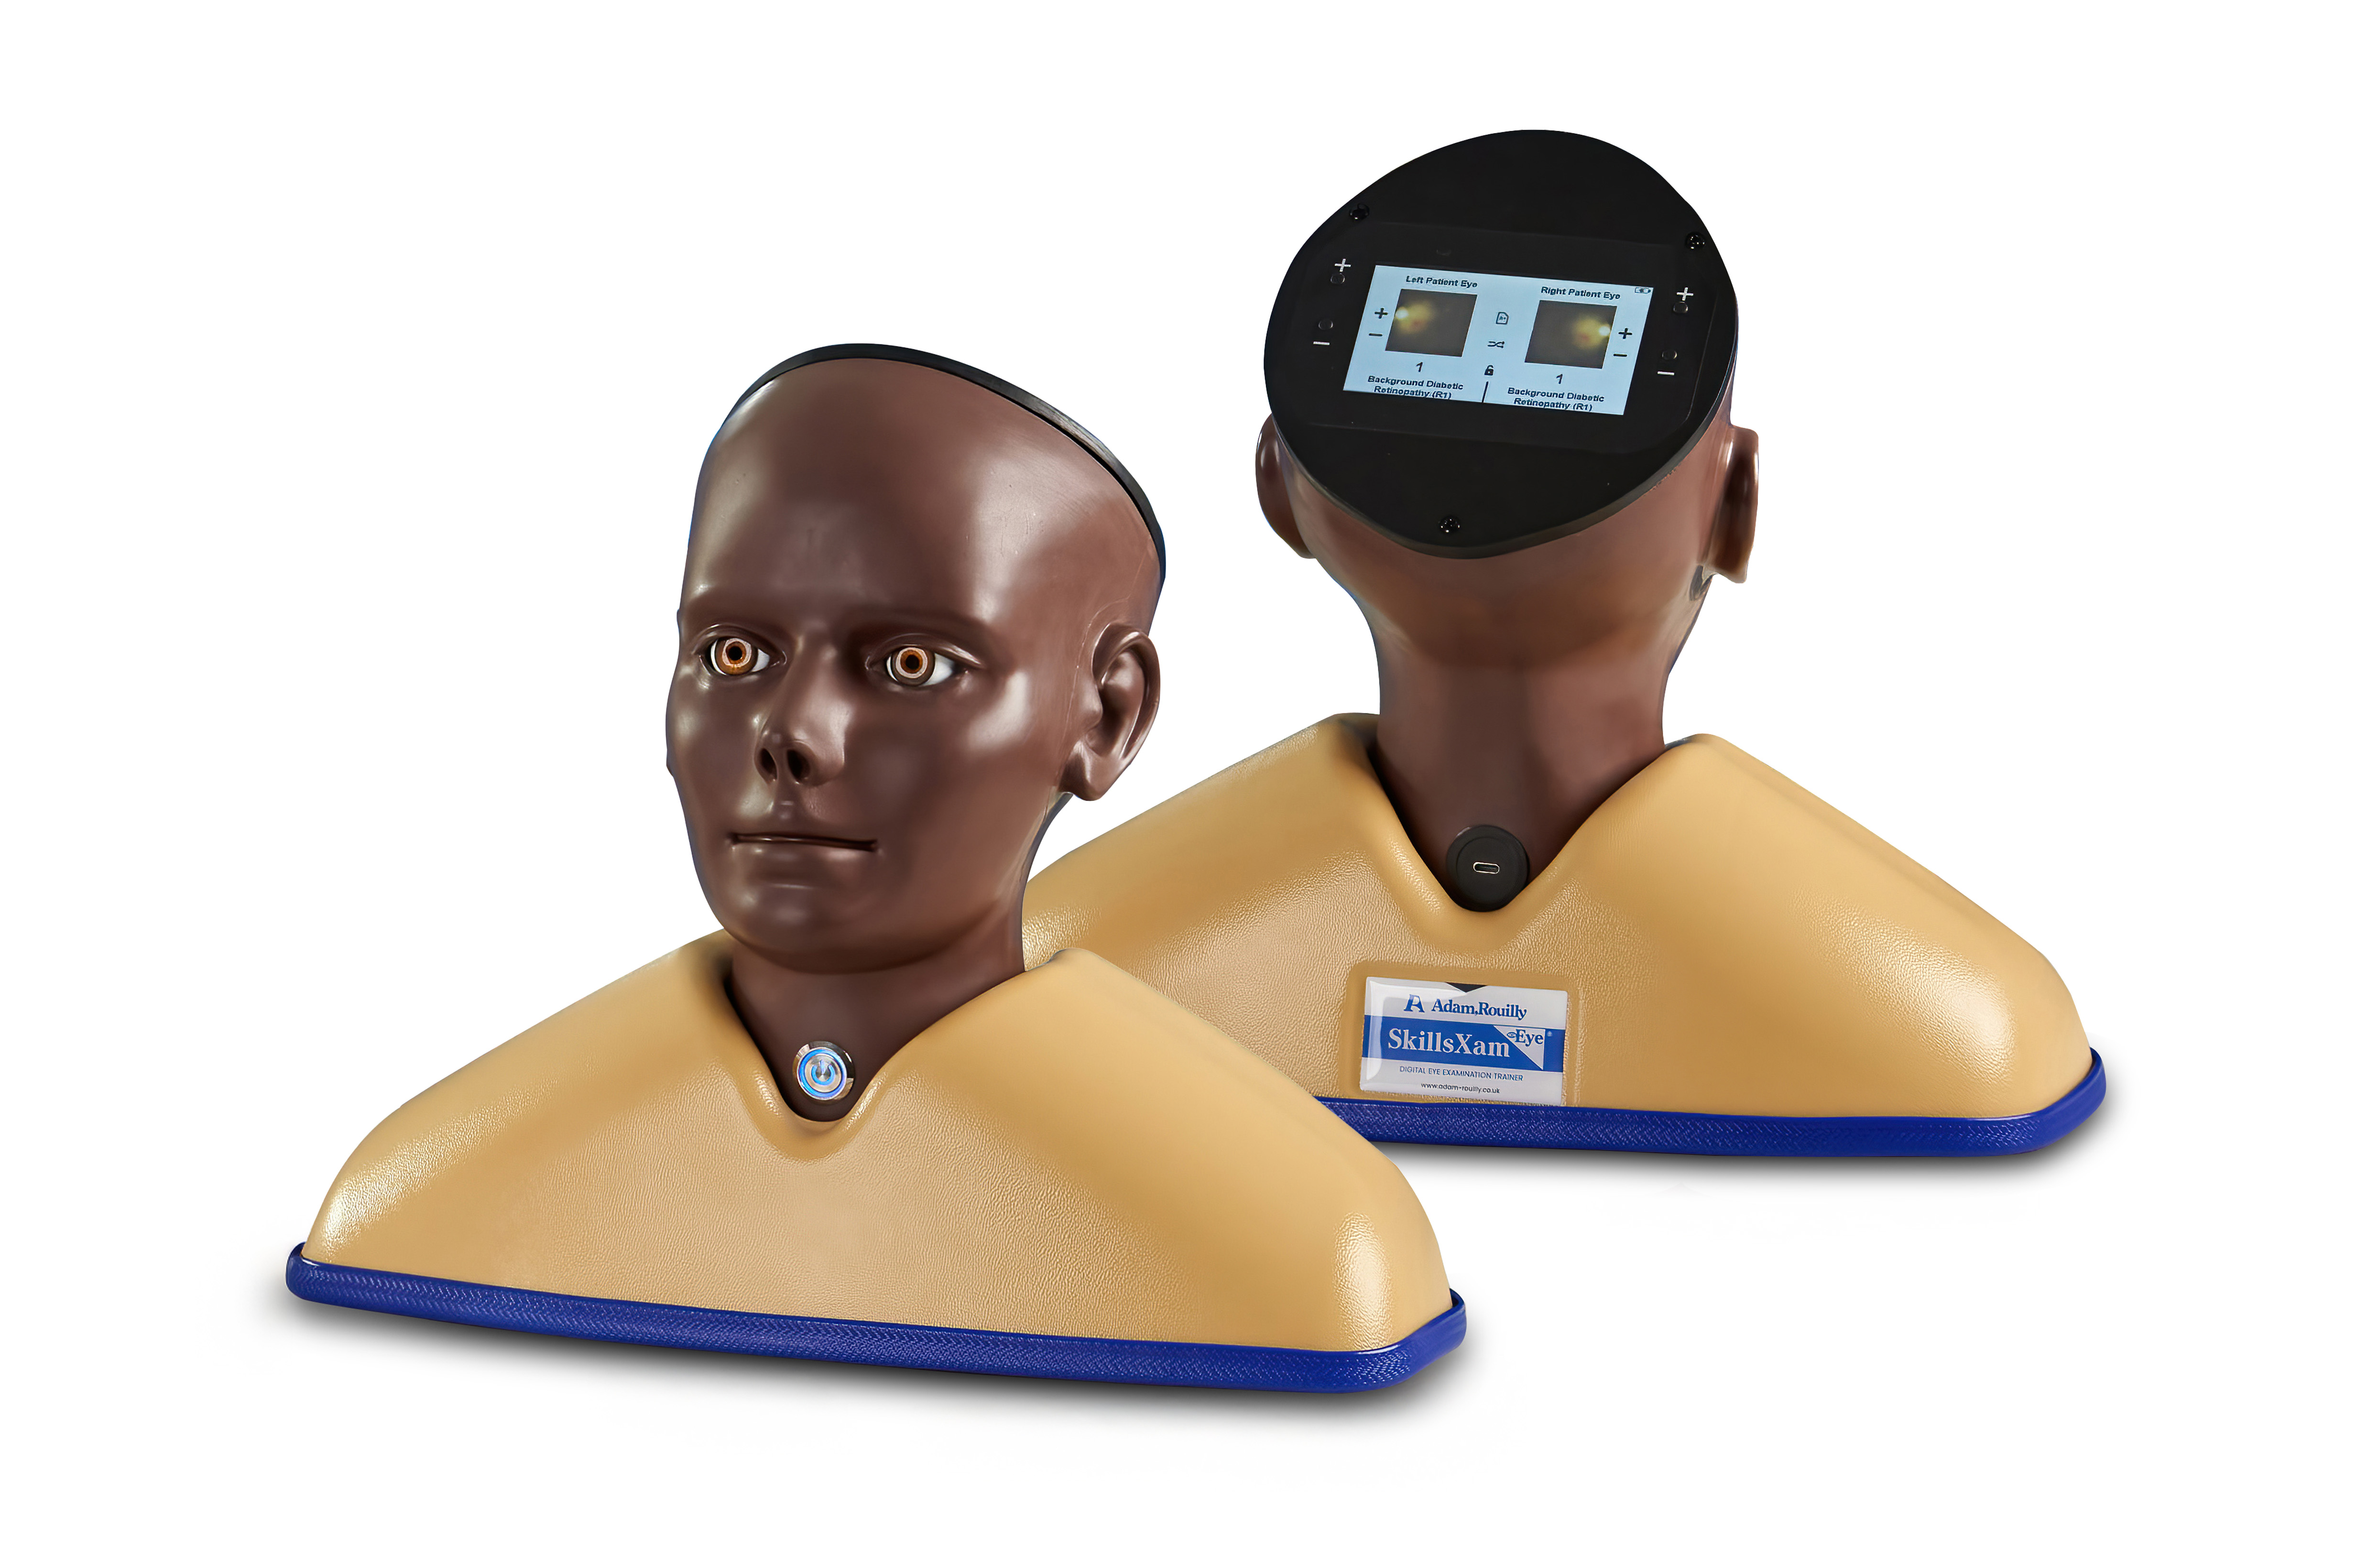

Enhanced Digital Eye Examination/Retinopathy Trainer, Dark

Developed in collaboration with Professor Vinod Patel, Professor, Diabetes and Clinical Skills, the Enhanced Digital Eye Examination Trainer takes ophthalmoscopy training to a new level of realism and inclusivity.

For the first time, advanced digital technology allows trainees to experience how the same eye condition can present differently in patients with light and dark skin tones. In darker-skinned patients, deeper pigmentation in the fundus reduces vessel visibility, a nuance replicated only in the AR503/50 Dark model. This provides learners with invaluable exposure to the clinical variations they will encounter in real practice, enhancing both competence and confidence. Offering two product versions enables trainees to gain an awareness of these visible variances.

Inside the model, conditions are displayed with greater clarity and true-to-life colour on high-resolution circular LCD screens. A 4.3-inch external touchscreen interface makes operation intuitive and effective, allowing users to preview, search, and select conditions or build customisable sets for teaching, self-directed learning, or examination scenarios.

The Enhanced Digital Eye Examination Trainer delivers an authentic, adaptive, and inclusive learning experience, redefining the standard in ophthalmoscopy training.